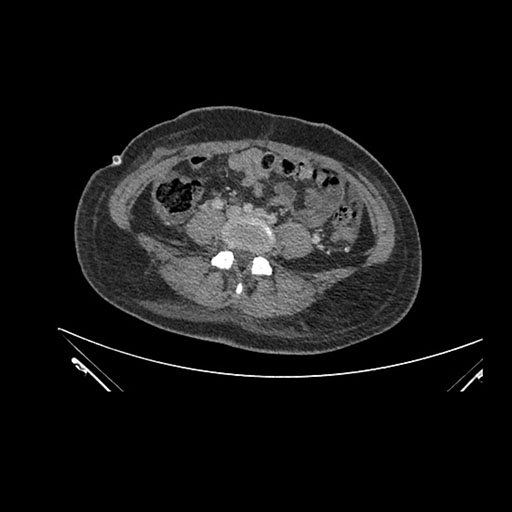

Axial Venous

Imaging analysis

Based on initial findings, which issue(s) would you be most concerned about?